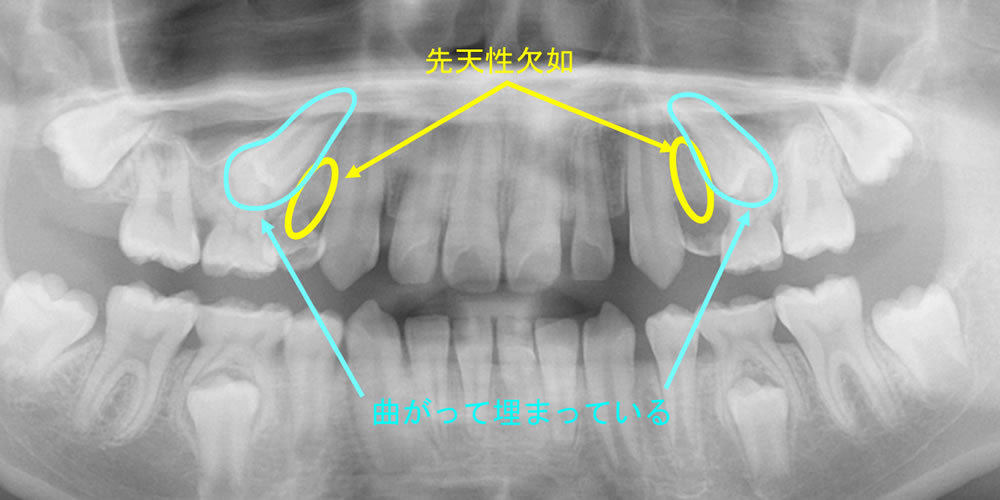

別症例(①②の参考症例)

こちらは、①先天性欠如、②曲がって埋まっている状態が上顎両側小臼歯部に併発している別の症例です。

先天性欠如:もともと生えてくるはずの永久歯がない

曲がって埋まっている(永久歯歯胚の位置異常、転位歯など):隣の歯に引っかかっているなど、正常に生えてこない